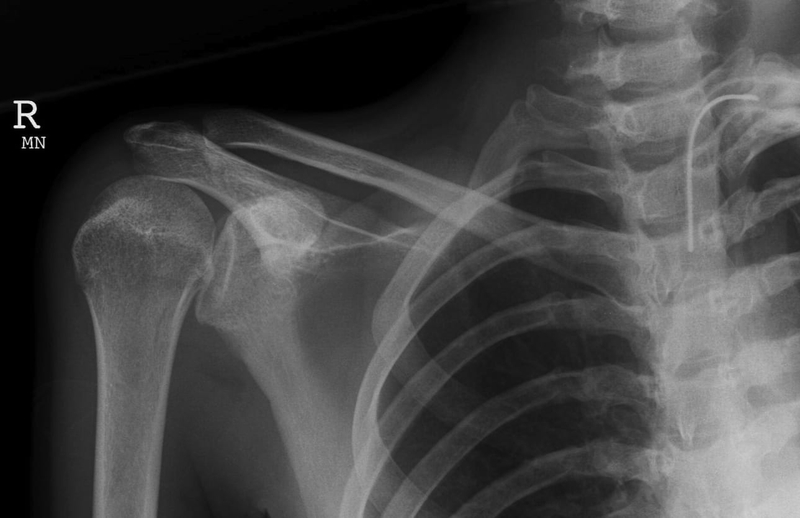

Trật vai ra sau

Vì xương bả vai án ngữ nên tình trạng này rất hiếm gặp, chỉ chiếm khoảng 5% các trường hợp. Thường xảy ra do ngã chống tay trong tư thế khép vai hoặc do bị động kinh, điện giật.

Hình ảnh trật khớp vai sau

Hình ảnh X-quang trật khớp vai sau